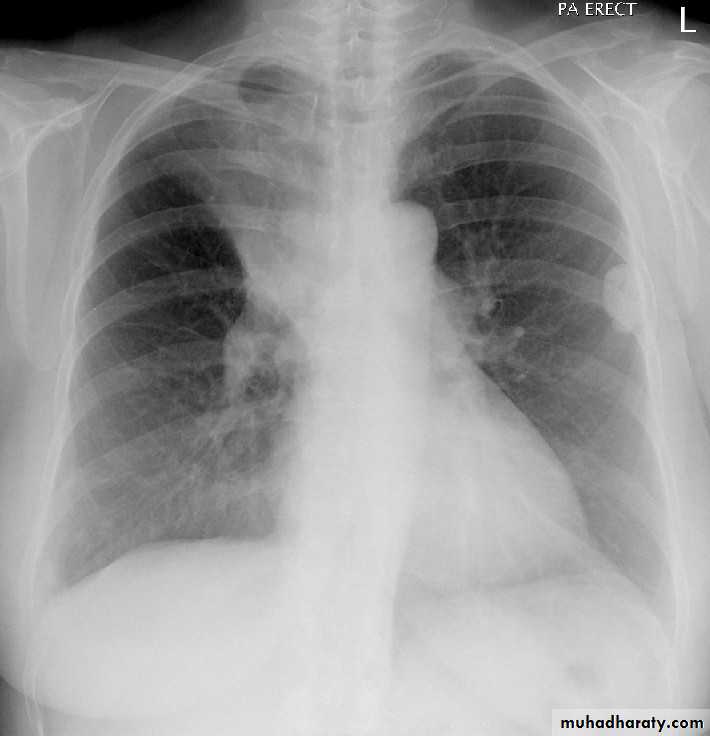

CT غير مطلوبbronchogenic carcinoma caused lung collapse

CXR of adult ,PA view shows:

Hilar mass +homogenus opacity in the upper right lobe with elevation of the horizontal fissure

Golden S sign

Shifting of the trachea to the same side